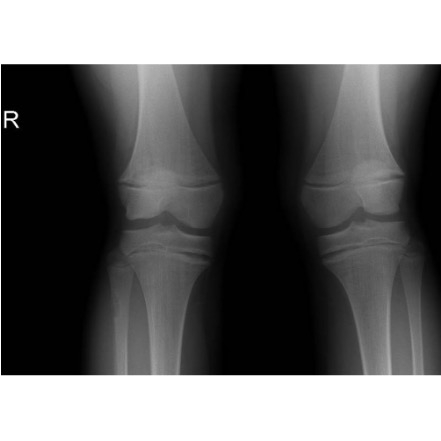

| The Kneediest Puzzle: Chronic Joint Pain With A Surprising Angle In A Young Girl - Page #3 | |||